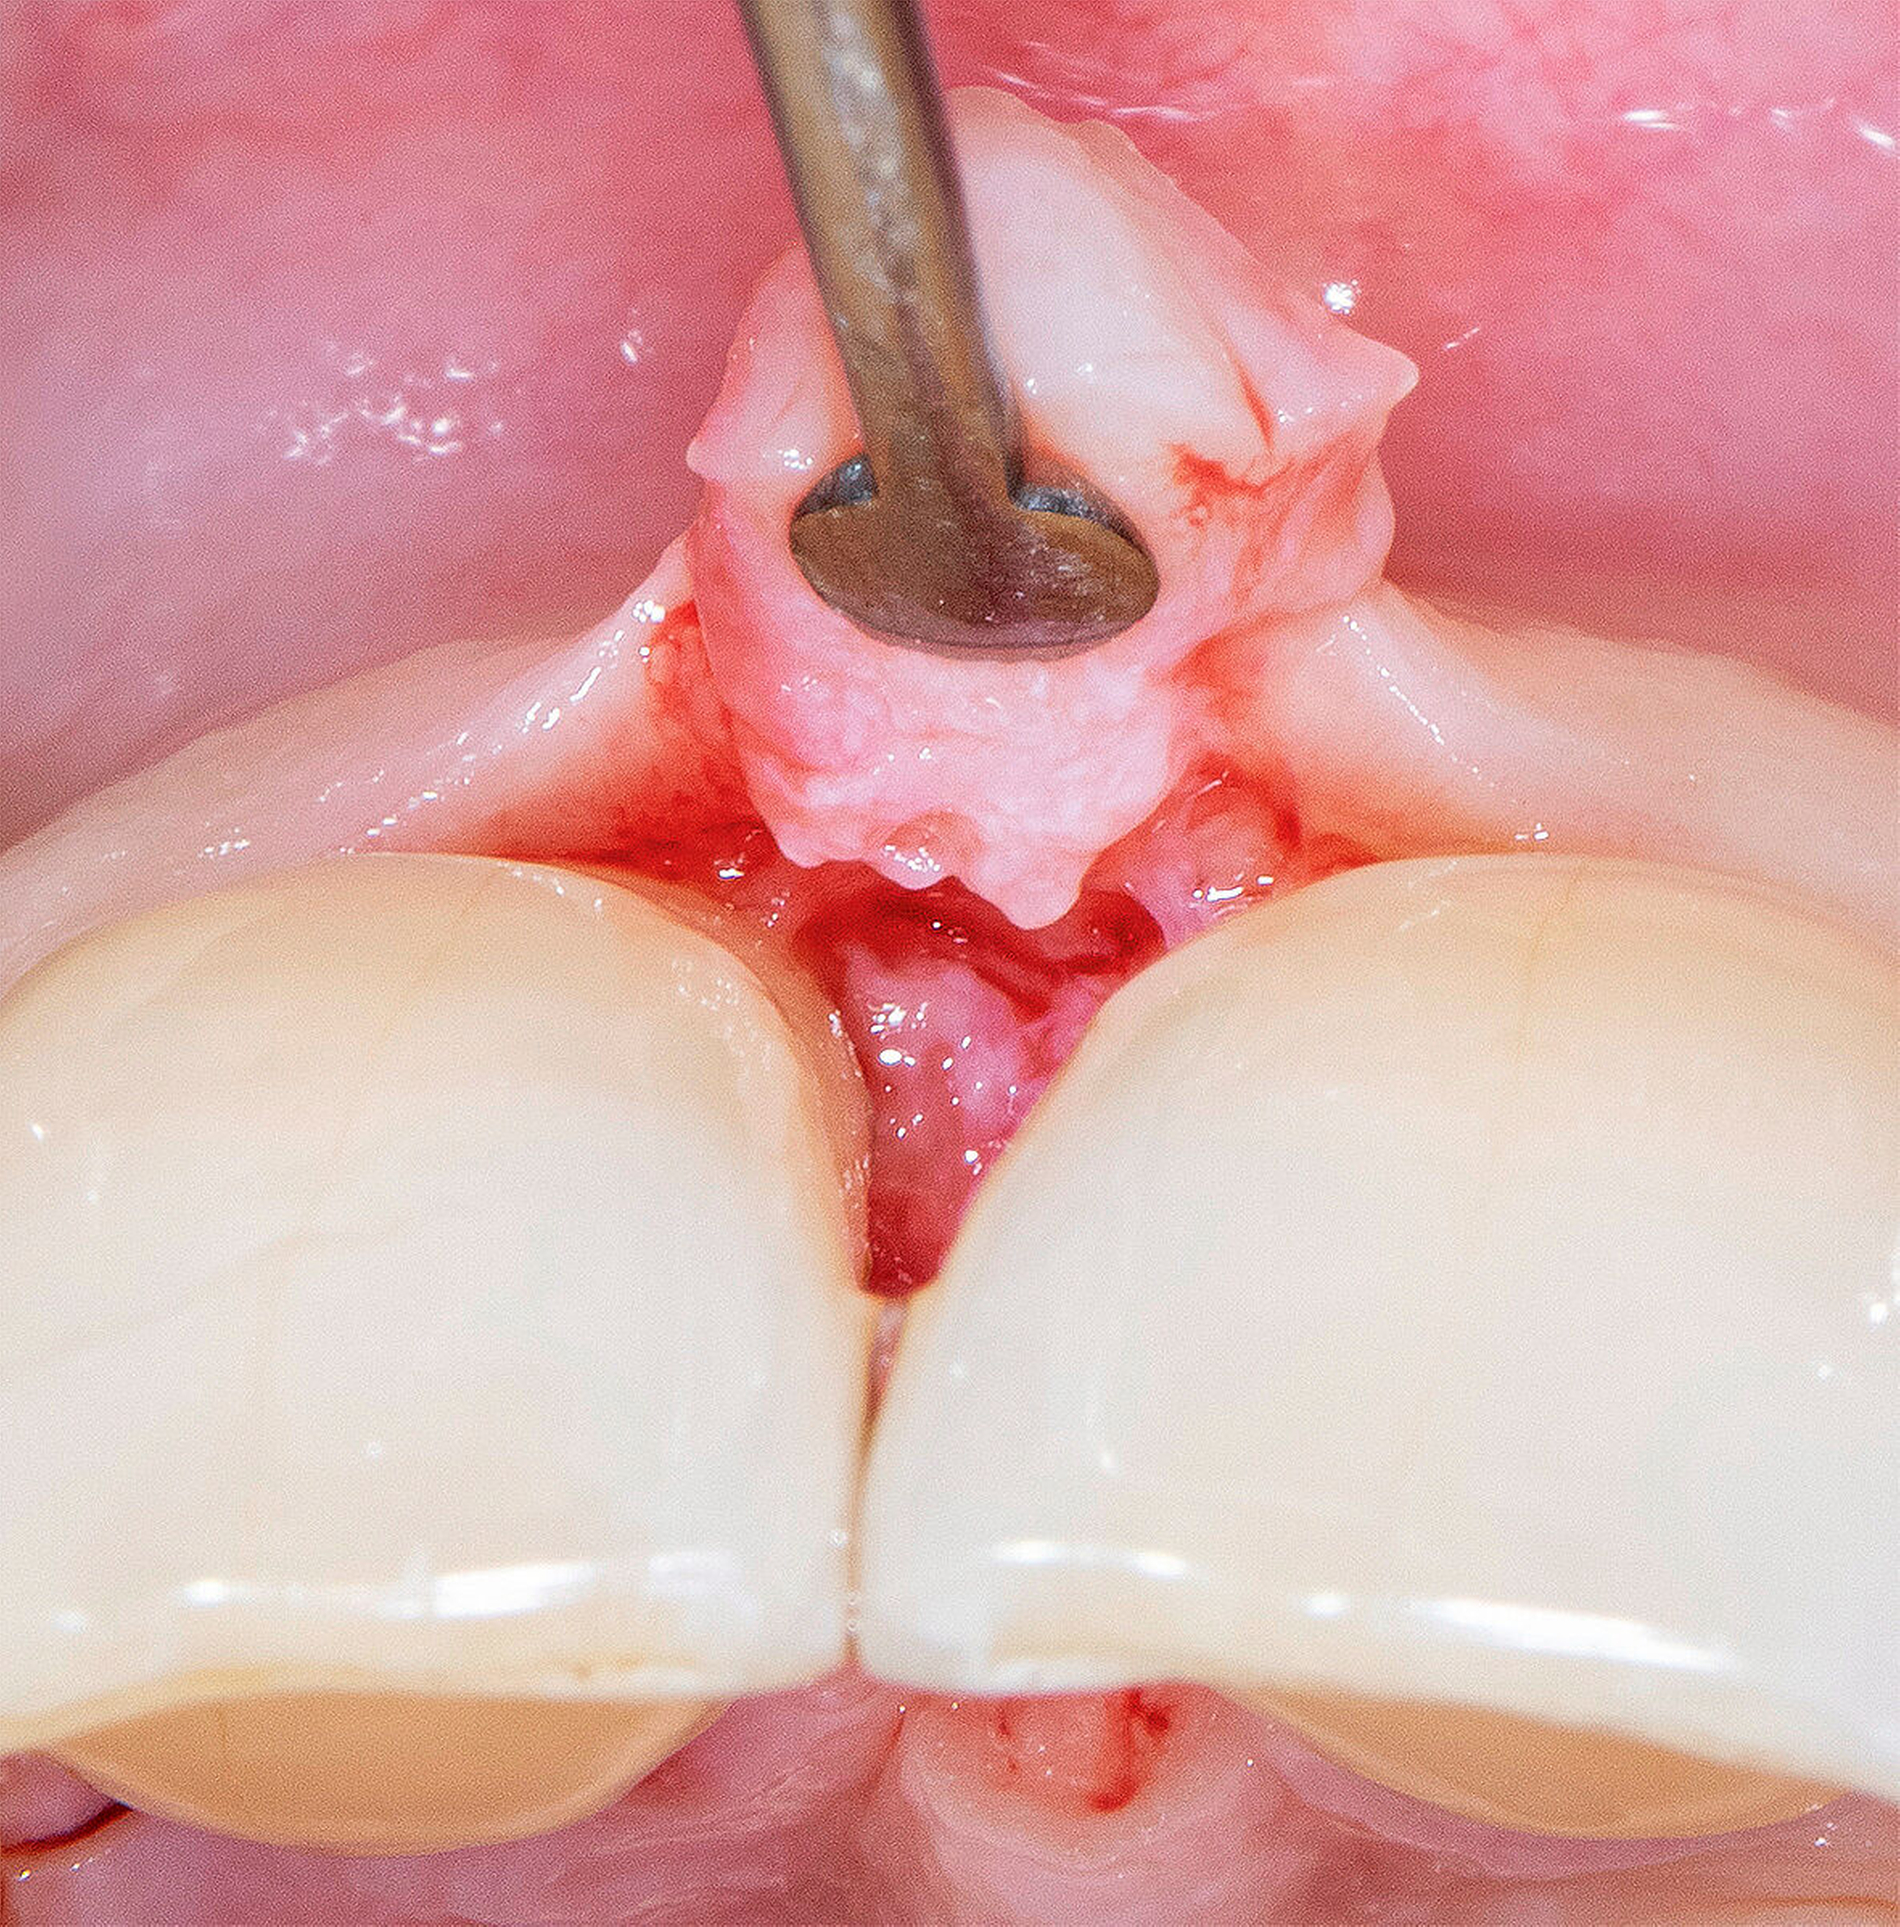

Bei einer Heilung per primam sind die Wundränder glatt, gut durchblutet, spannungsfrei aneinander liegend und präzise adaptiert. In der initialen, hämostatischen Phase bildet sich ein dünnes Blutgerinnsel zwischen den Wundrändern. Die Anhaftung dieses Koagulums fungiert als Abwehr gegenüber mechanischen Belastungen auf die präparierten Lappen [Wikesjö et al., 1991]. Blutplättchen geben Wachstumsfaktoren ab, die die Heilung einleiten. Es bildet sich eine Matrix aus weißen Blutkörperchen, die die Wunde bedeckt. Es kommt zu einer leichten Entzündungsreaktion, in deren Folge meist keine Gewebeschädigung verursacht wird. Die Gefahr einer bakteriellen Infiltration wird durch den Verschluss im oberflächlichen Bereich der Wunde nahezu vollständig vermieden [Cortellini & Tonetti, 2009]. Die Bildung von Narben- oder Granulationsgewebe wird minimiert, eine vollständige Ausheilung der Wundregion und eine Wiederherstellung der Gewebe ermöglicht (Abbildung 1).

Neue Trends und Entwicklungen in der modernen Oralchirurgie gehen allerdings in Richtung sehr feiner Skalpellklingen, die extrem kleine chirurgische Zugänge ermöglichen und noch weniger invasive mikrochirurgische Techniken erlauben [Rebele et al., 2014; Zuhr et al., 2018]. Auf dieser Grundlage lässt sich vermuten, dass die mikrochirurgischen Instrumente und Nahtmaterialien in der oralen Mikrochirurgie in Zukunft wieder kleiner werden könnten und deshalb auch wieder höhere Vergrößerungsfaktoren für die zu ihrer Anwendung erforderlichen Sehhilfen notwendig werden (Abbildungen 5 bis 16). So wie es in anderen mikrochirurgischen Fachdisziplinen bereits heute Realität ist, könnten vor diesem Hintergrund auch zukünftige Generationen dentaler Operationsmikroskope im Hinblick auf Flexibilität, Workflow und Anwenderfreundlichkeit verbessert und auf diese Weise wieder einen festen Platz in einer oralchirurgisch tätigen Praxis einnehmen. Eine gute Perspektive könnten auch innovative Lupensysteme darstellen, die bereits heute mit Vergrößerungsfaktoren von 9.0x bis 10.0x angefertigt werden können.